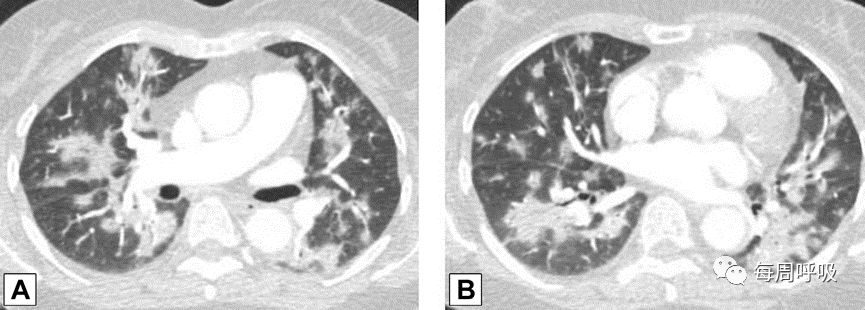

图2 外周实变。2例患者CT轴位平扫图像。A,这张图片显示了一名女性右肺上叶周围实变,她曾因乳腺癌接受过放射治疗,并经活检证实为机化性肺炎(OP)。B,此图像显示左肺下叶和舌叶周围实变,活检证实为继发于淋巴瘤化疗的OP。

图3 支气管血管束分布 在活检证实的机化性肺炎患者中,通过中(A)和下(B)肺区的轴位增强CT扫描图像显示双侧多灶性支气管血管周围实变灶。